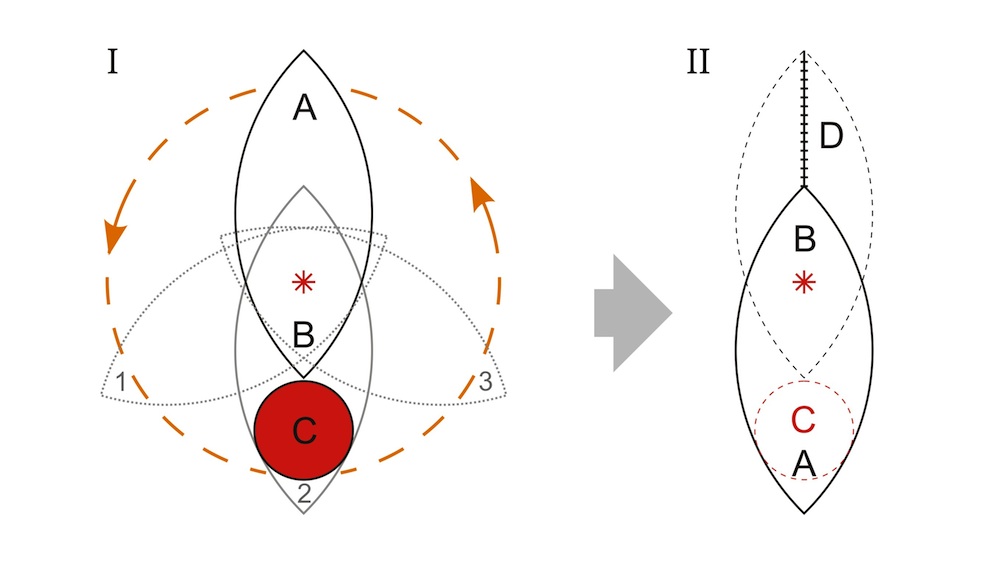

Таким образом, лоскуты типа пропеллер относятся к островковому типу лоскутов, которые после дессекции перемещаются в реципиентное ложе путем аксилярной ротации на питающей ножке таким образом, чтобы больший лепесток лоскута обеспечивал закрытие раневого дефекта (С) в реципиентной зоне, а меньший – закрытие донорской зоны (D) без существенного натяжения краев кожи (Рис. 3).

Рис. 3. Схема планирования и перемещения лоскута типа пропеллер для закрытия раневого дефекта; I – Позиция раневого дефекта (С) и лоскута (АВ) до проведения операции, звездочкой обозначена точка выхода перфорантной ветви артерии, которая формирует питающую ножку, определяет центр ротации (point pivot) и соотношение долей в лоскуте (большая доля А-звездочка и малая доля В-звездочка); Круговой стрелкой показана возможная степень ротации (90 град – 180 град.); II – Позиция лоскута (АВ) после его выделения и ротации на 180 град. в реципиентную зону, раневой дефект (С) полностью закрыт без натяжения тканей большой долей лоскута (А-звездочка), также проведено первичное ушивание донорской зоны (D) с использованием малой доли (В-звездочка).